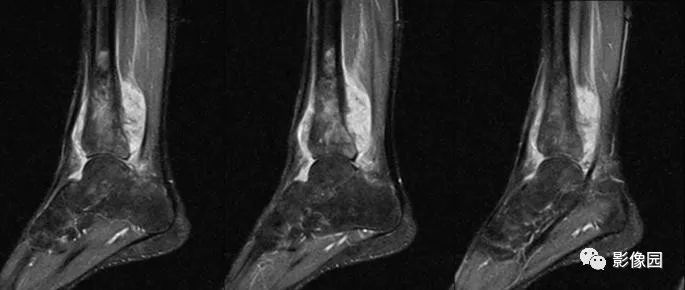

【影像学检查】2016-01-05

评论:前片X线示左胫骨下段及干骺端病变,髓腔内密度不均匀增高,内侧骨皮质可见骨质破坏,可见骨膜反应。CT示病灶内见多发斑片状肿瘤骨(黄色箭头),周围可见针状骨膜反应(红色箭头)。周围软组织肿胀。MRI示胫骨下段以长T1、长2信号为主的混杂信号影,未跨越胫距关节面,周围未见明显软组织肿块。周围软组织广泛片状长T1长T2信号影。复查X线示病变较前片明显进展,左侧胫骨远段及干骺端骨质破坏,周围可见针状骨膜反应及Codman三角(蓝色箭头)形成。相邻左侧腓骨下端、距骨滑车受累。